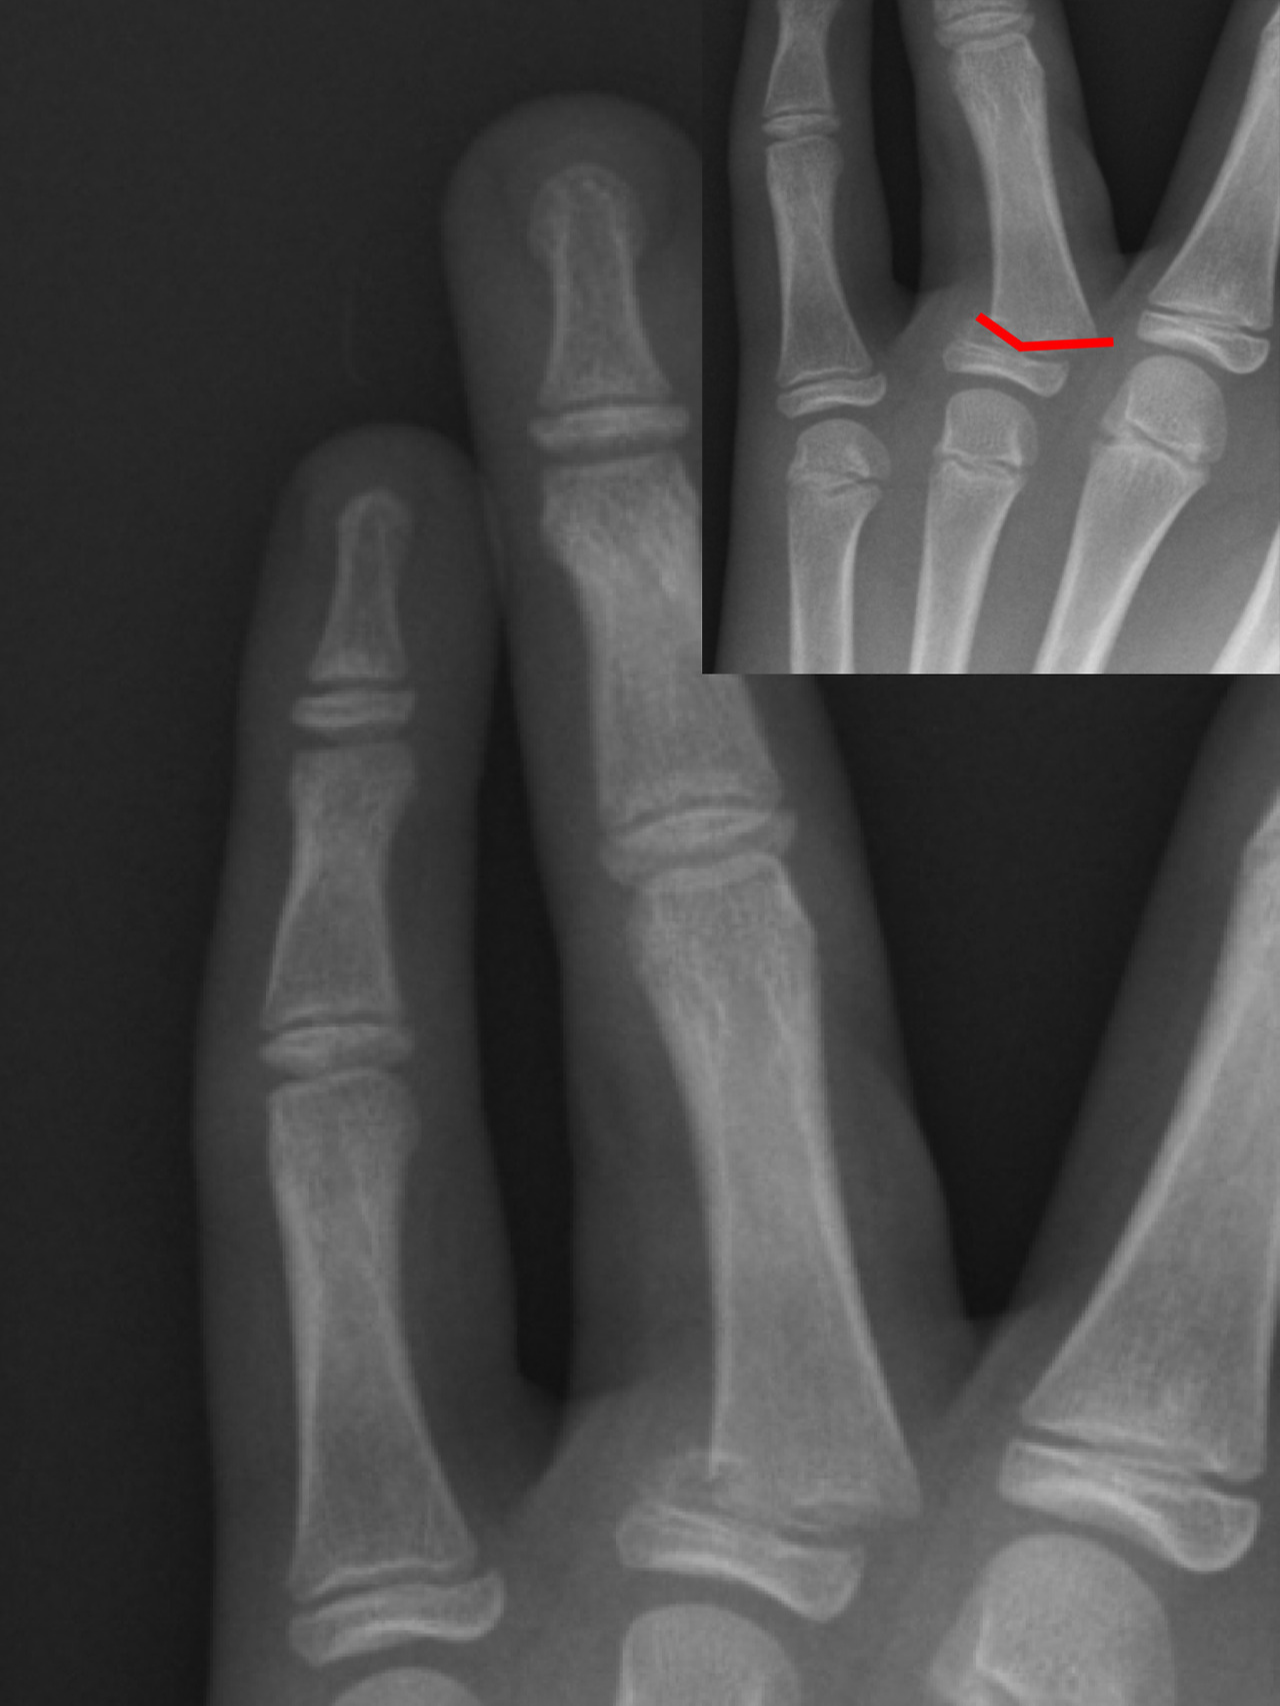

손가락 골절은 기저부(base) 골절, 중간부(shaft) 골절, 관절면(intra-articular) 골절 등으로 나뉘며, 특히 관절면을 침범한 골절은 기능적 후유증이 남을 위험이 높습니다. 따라서 엑스레이 검사로 정확한 위치와 손상 정도를 파악하고, 필요 시 CT나 초음파로 인대 손상 여부를 함께 확인해야 합니다.

손가락에 금이 갔을 때 중요한 것은 정확한 진단입니다. 단순히 통증이 있다고 해서 자가진단으로 테이핑만 하는 것은 위험하며, 반드시 엑스레이 검사를 통해 뼈의 정렬 상태와 골절선을 확인해야 합니다.